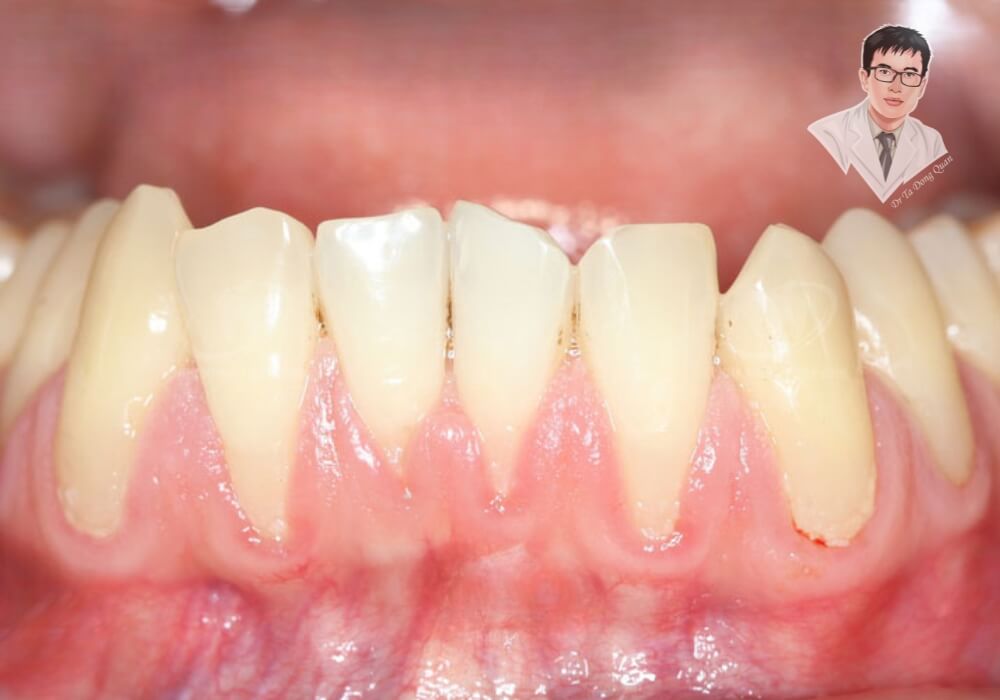

Tụt nướu lộ chân răng là tình trạng phổ biến gây ảnh hưởng nghiêm trọng đến sức khỏe răng miệng. Khi mô nướu bị rút xuống, phần chân răng bị lộ ra ngoài, không còn được bảo vệ như bình thường. Điều này không chỉ làm mất đi vẻ thẩm mỹ của nụ cười mà còn khiến răng trở nên nhạy cảm, dễ bị viêm nhiễm và tổn thương do vi khuẩn. Nếu không điều trị kịp thời, tụt nướu lộ chân răng có thể dẫn đến viêm nha chu, sâu chân răng và thậm chí mất răng vĩnh viễn. Việc hiểu rõ nguyên nhân, dấu hiệu nhận biết và các phương pháp điều trị sẽ giúp bạn bảo vệ sức khỏe răng miệng tốt hơn.

- Tụt nướu lộ chân răng là hiện tượng mô nướu dần co rút, để lộ phần chân răng vốn được bảo vệ bởi nướu.

- Khi nướu răng bị tụt, răng trở nên dài hơn bình thường, dễ bị kích thích khi ăn uống.

- Tình trạng này làm tăng nguy cơ viêm nha chu, mất nướu răng, ảnh hưởng đến chức năng nhai và thẩm mỹ răng miệng.

- Nếu không có biện pháp điều trị, tụt nướu lộ chân răng có thể gây tiêu xương ổ răng, khiến răng lung lay và mất đi sự nâng đỡ cần thiết.

- Nướu răng bị tụt, khiến răng trông dài hơn bình thường.